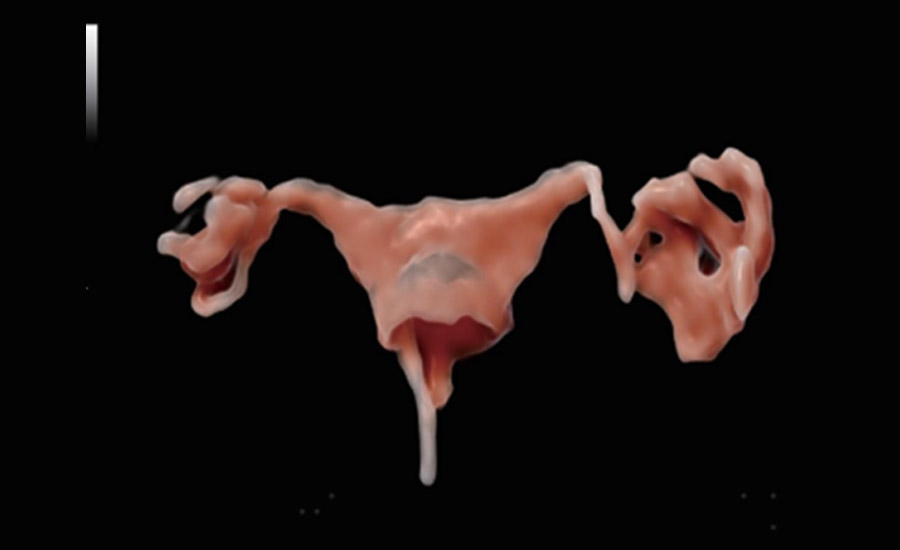

UMA (angiografia ultramicroscĆ³pica)

A tecnologia inovadora elimina as limita??es das tradicionais imagens com Doppler. Com resolu??o espacial e sensibilidade de fluxo ultra-altas, permite a detec??o de perfus?es de fluxos muito sutis e lentos, ampliando assim a aplica??o clĆnica da avalia??o qualitativa e quantitativa do ultrassom no cĆ©rebro fetal, rins, placentas, endomĆ©trios, ovĆ”rios etc.

Por meio da combina??o de algoritmos avan?ados e do conhecimento especĆfico da regi?o, a inovadora solu??o Smart Scene permite a identifica??o automĆ”tica das caracterĆsticas do tecido e fornece diagnĆ³stico especĆfico dos Ć³rg?os com informa??es completas. Com base na identifica??o automĆ”tica de cenĆ”rios, a solu??o realiza n?o apenas a varredura 2D inteligente com configura??es e medidas automĆ”ticas, mas tambĆ©m oferece informa??es 3D abrangentes em todas as etapas, desde a otimiza??o de imagens volumĆ©tricas atĆ© a difĆcil obten??o de planos 2D, e a quantifica??o durante todo o procedimento. Ele ajuda a reduzir em grande parte a dependĆŖncia de habilidades clĆnicas, ao mesmo tempo que aumenta a precis?o, a confian?a e a eficiĆŖncia no diagnĆ³stico.